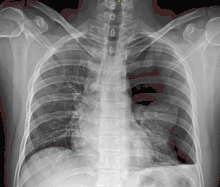

![]() تبين الأشعة السينية للصدر وجود استرواح الصدر على اليمين (يسار الصورة)، حيث تبين أيضًا غياب علامات الرئة لوجود هواء حر داخل الصدر. A large right-sided spontaneous pneumothorax (left in the image). An arrow indicates the edge of the collapsed lung | |

الأشعة السينية على الصدر

عادة ما يكون التصوير الشعاعي العادي للصدر، بإشعاع الأشعة السينية من الخلف (من الخلف للأمام) هو أنسب فحص في البداية. وعادة ما يتم تنفيذ ذلك خلال الشهيق (مع كتم النَفَس). لأن التصوير بالأشعة السينية أثناء الزفير (بعد خروج الهواء) لا يعطي أي معلومات إضافية.[12][13] إذا لم تُظهر الأشعة السينية الساقطة من الخلف للأمام استرواح صدري، ولكن كان هناك شكوك قوية في وجوده، يتم عمل أشعة سينية جانبية ( بإسقاط الأشعة من الجانب)، ولكن هذه ليست الطريقة الروتينية.[13][17] ومن المألوف وجود انحراف المنصف (التركيب بين الرئتين التي يحتوي على القلب، والأوعية الدموية الكبيرة، والممرات الهوائية الكبيرة) بعيدا عن الرئة المتضررة بسبب اختلافات الضغط. لذا فإن هذا الانحراف ليس دليلا على حدوث استرواح الصدر الضاغط، إنما يتحدد أساسا عن طريق مجموعة من الأعراض بالإضافة إلى نقص الأكسجين، والصدمة.[12]

يمكن تحديد حجم استرواح الصدر (أي حجم الهواء في الفضاء الجنبي) بدرجة معقولة من الدقة عن طريق قياس المسافة بين جدار الصدر والرئة، ويتم على أساسه تحديد العلاج، لأنه يتم التعامل مع وجود استرواح صدري أصغر بشكل مختلف. وجود طبقة رقيقة من الهواء حجمها 2 سم يعني أن استرواح الصدر يحتل حوالي 50٪ من نصف الصدر.[13] وقد ذكرت المبادئ التوجيهية المهنية البريطانية أن القياس يجب أن يتم على مستوى باب الرئة (مكان دخول الأوعية الدموية والمسالك الهوائية في الرئة) باعتبار 2سم كنقطة فاصلة،[13] في حين تنص المبادئ التوجيهية الأمريكية أن القياس ينبغي أن يتم من قمة الرئة مع التفريق بين استرواح الصدر "الصغير" و "الكبير" بفاصل 3سم.[23] ولكن قد تبالغ الطريقة الأخيرة في حجم استرواح الصدر إذا كان يقع أساسا في القمة، وهو أمر شائع.[13] الروابط بين طرق القياس المختلفة ضعيفة، ولكن هي أفضل الطرق المتاحة السهلة لتقدير حجم استرواح الصدر.[13][17] يمكن أن يساعد المسح المقطعي (انظر أدناه) في تحديد حجم استرواح الصدر بدقة أكبر، ولكن لا يوصى باستخدامه الروتيني مع هذه الحالات.[23]

ليس كل استرواح صدري مثل الآخر، فقد لا يشكل بعضها سوى تجويف من الهواء في مكان معين في الصدر فقط.[13] كما يمكن ملاحظة كميات صغيرة من السوائل في الأشعة السينية على الصدر (استرواح الصدر الموهي)، وقد يكون هذا السائل دم.[12] في بعض الحالات، قد يكون الشيء الوحيد غير الطبيعي في الأشعة هو "علامة التلم العميق"، التي تظهر فيها المساحة الصغيرة الموجودة عادة بين جدار الصدر والحجاب الحاجز كبيرة بسبب الوجود غير الطبيعي للسوائل.[14]